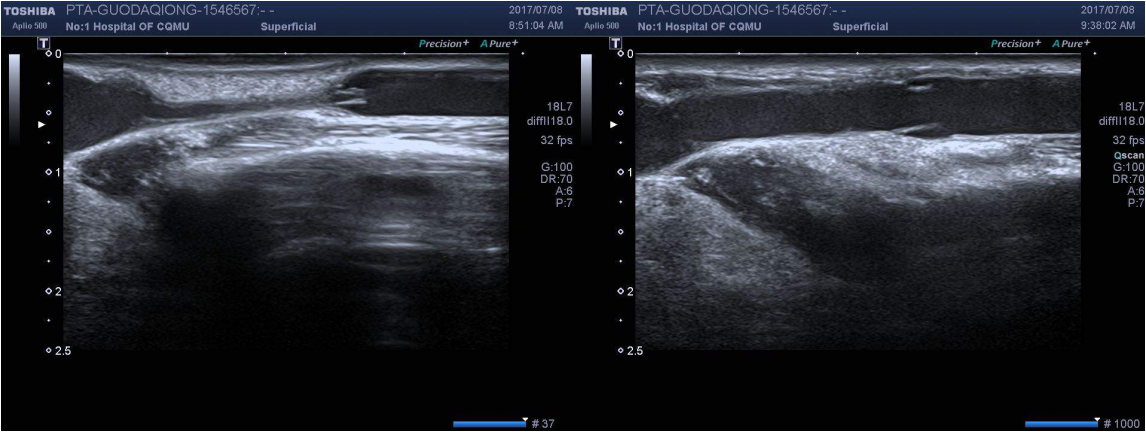

PTA手术B超示意图(左图为狭窄静脉,右图为球囊扩张后)